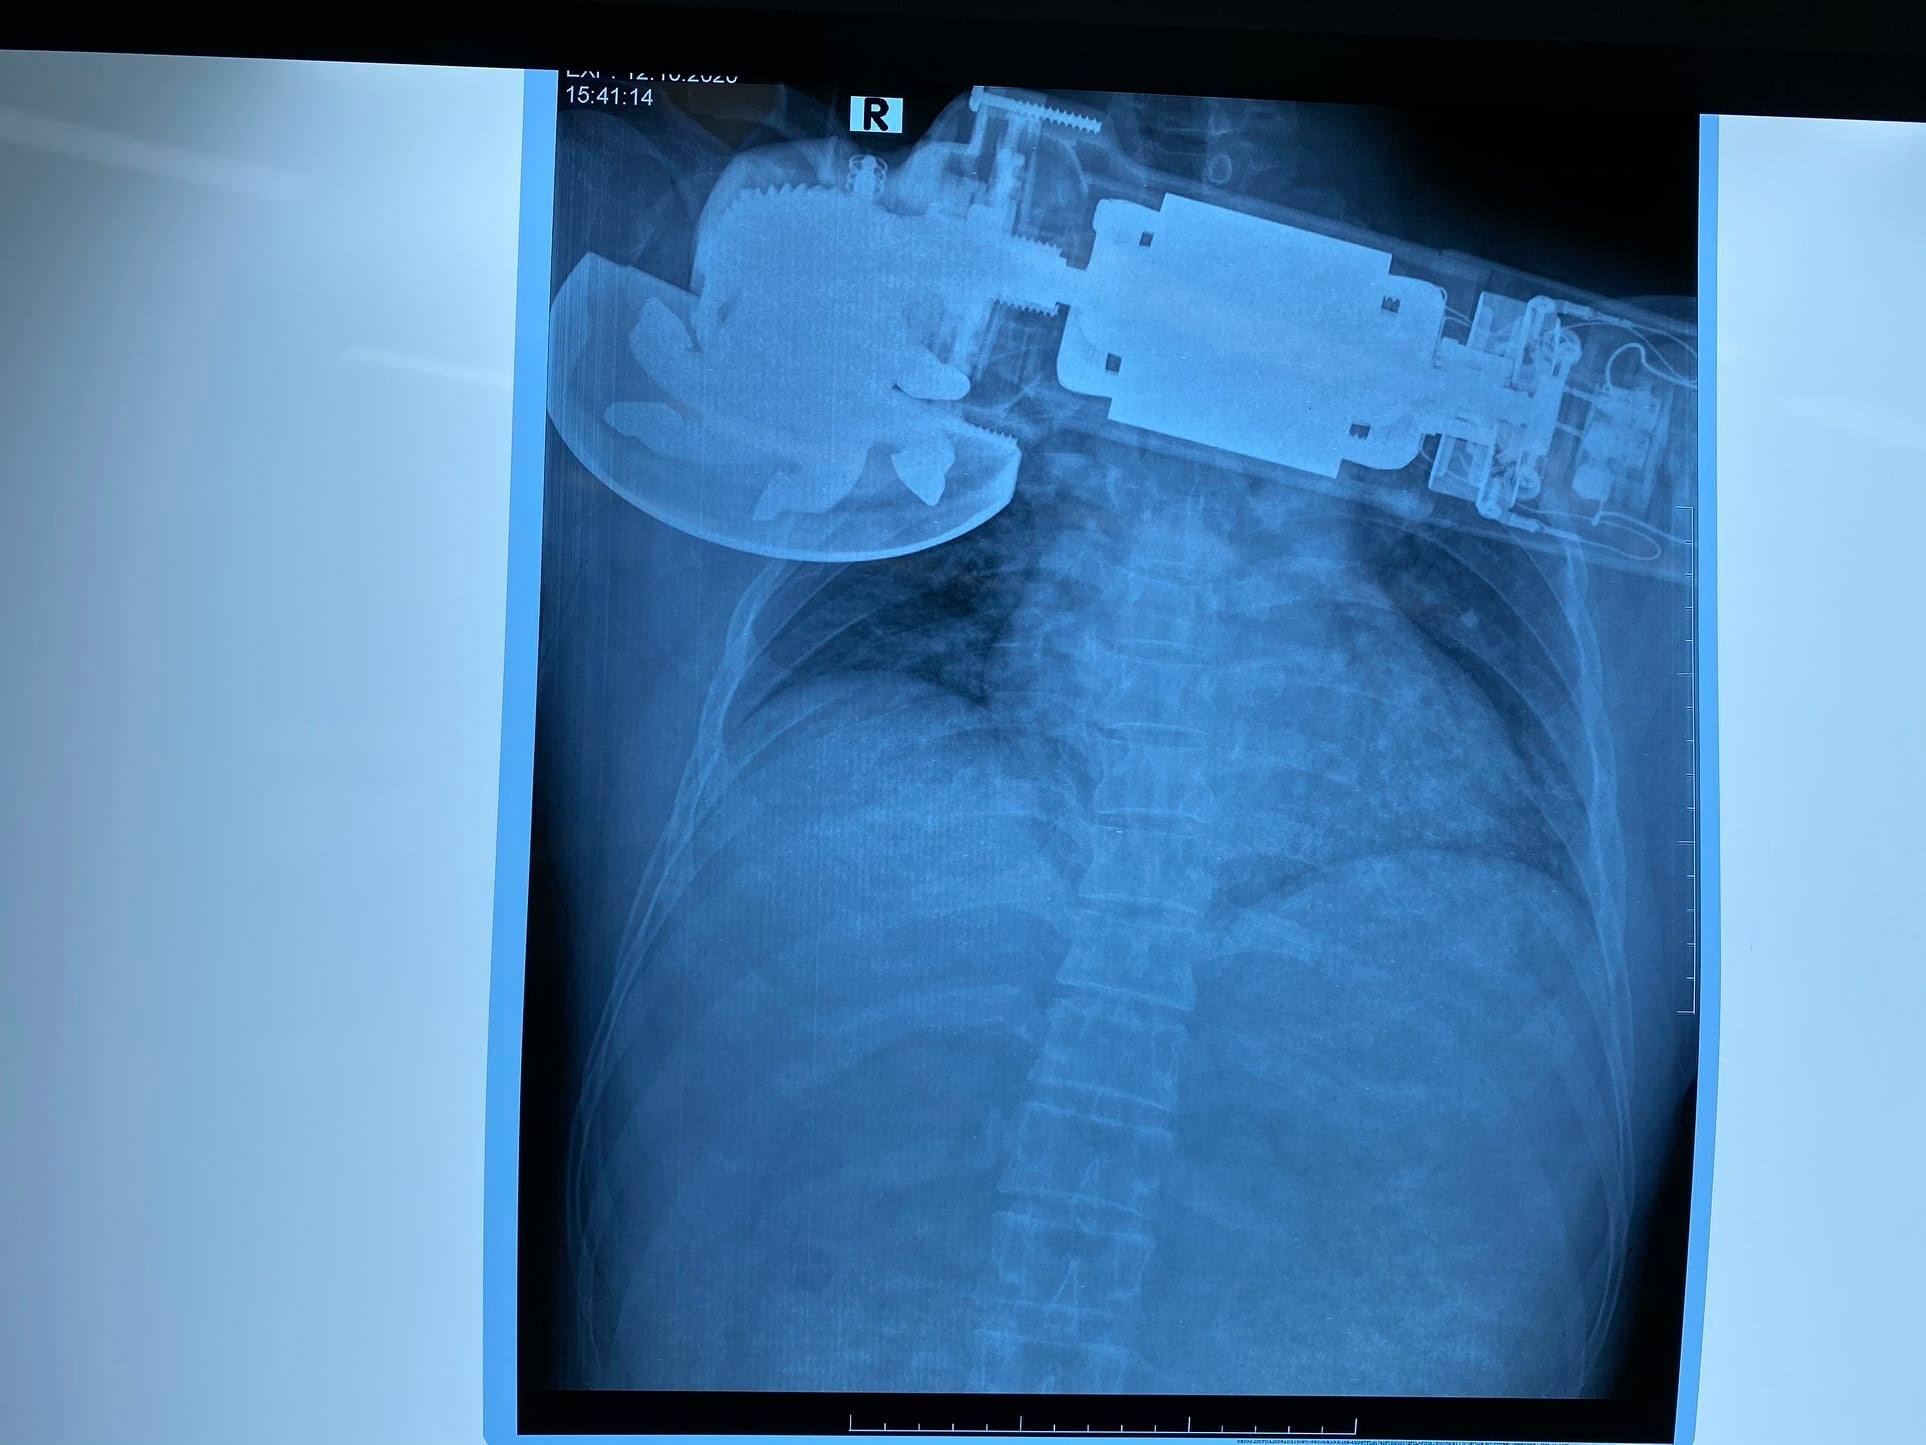

Mới đây, Bệnh viện Trung ương Quân đội 108 (Hà Nội) tiếp nhận bệnh nhân trú tại Bắc Ninh, bị máy chà văng và cắm vào ngực bên phải. Bệnh nhân nhập viện trong tình trạng tỉnh, không chảy máu, huyết động ổn.

Sau khi khám, các bác sĩ nhận định máy chà găm sâu vào thành ngực phải, sát bờ dưới xương, mép vết thương nham nhở. Phần mềm thành ngực bị cuốn vào trong máy chà gây khuyết hổng, mất và bầm dập vùng da quanh tổn thương. Bệnh nhân được chỉ định mổ cấp cứu.

Bệnh nhân bị máy chà văng và cắm vào ngực bên phải. Ảnh: BVCC.

Trong quá trình xử trí, các bác sĩ nhận thấy có tổn thương đứt bán phần của cơ ngực lớn, cơ ngực bé và cơ gian sườn 2. Do đó, ê-kíp phẫu thuật đã cắt lọc, khâu lại những tổn thương bị đứt, rách của những bộ phận này, rửa sạch khu vực mổ và khâu vết thương phần mềm.